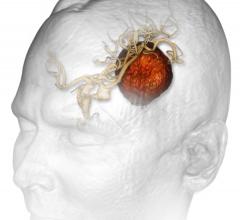

Cancer patients with limited brain metastases (one to four tumors) 50 years old and younger should receive stereotactic radiosurgery (SRS) without whole brain radiation therapy (WBRT), according to a study in the March 15, 2015 issue of the International Journal of Radiation Oncology • Biology • Physics (Red Journal).